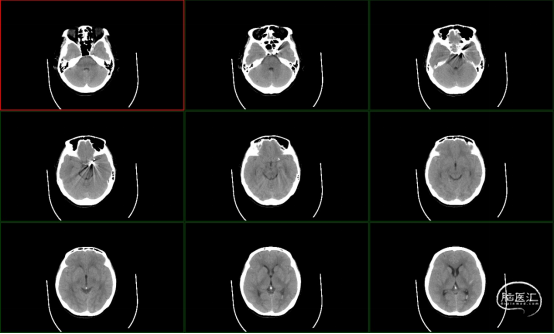

辅助检查:颅脑CT检查提示蛛网膜下腔出血。

术前CT

术后2天CT